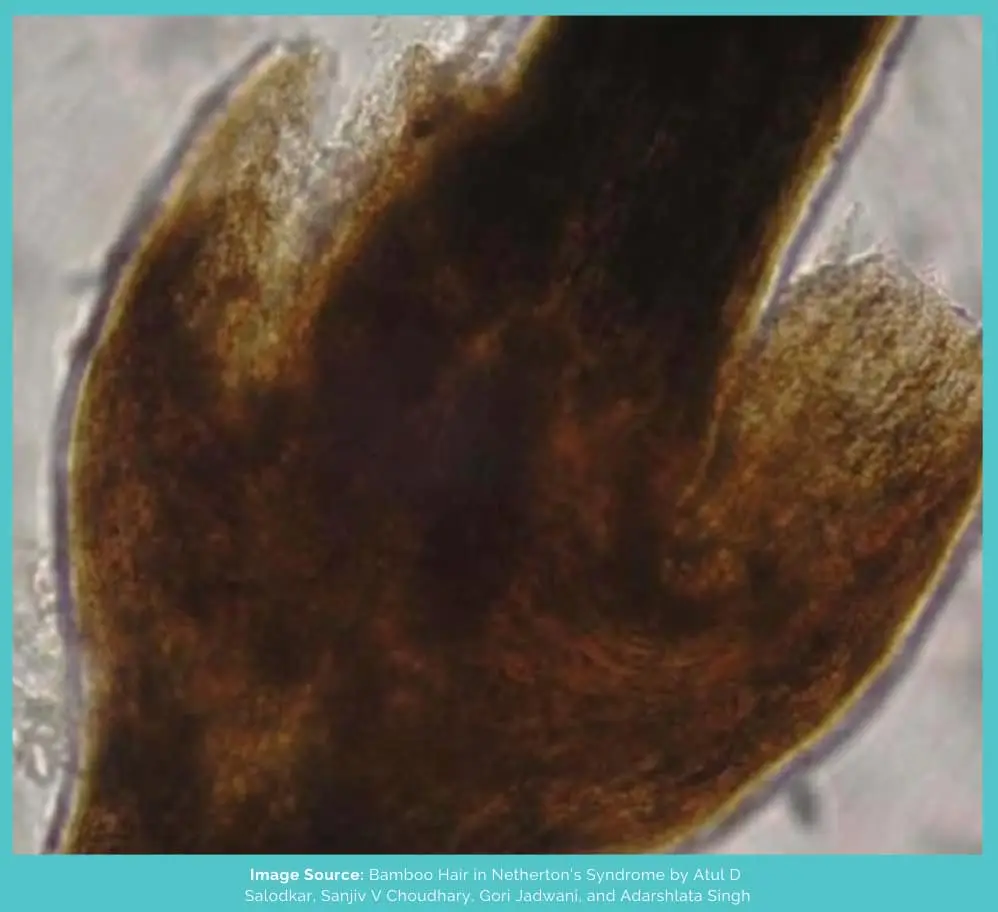

Trichorrhexis invaginata is a hair shaft abnormality in which the distal end (towards the tip) of the hair invaginates (or encloses) around the proximal end (towards the root).

As a result, a ball-and-socket joint-type formation is seen on the hair, and if it breaks from there, it ends up looking like a golf tee (the thing on which the ball is placed in golf).

Because these nodes end up resembling the nodes on a bamboo plant, it’s also known as “bamboo hair.”